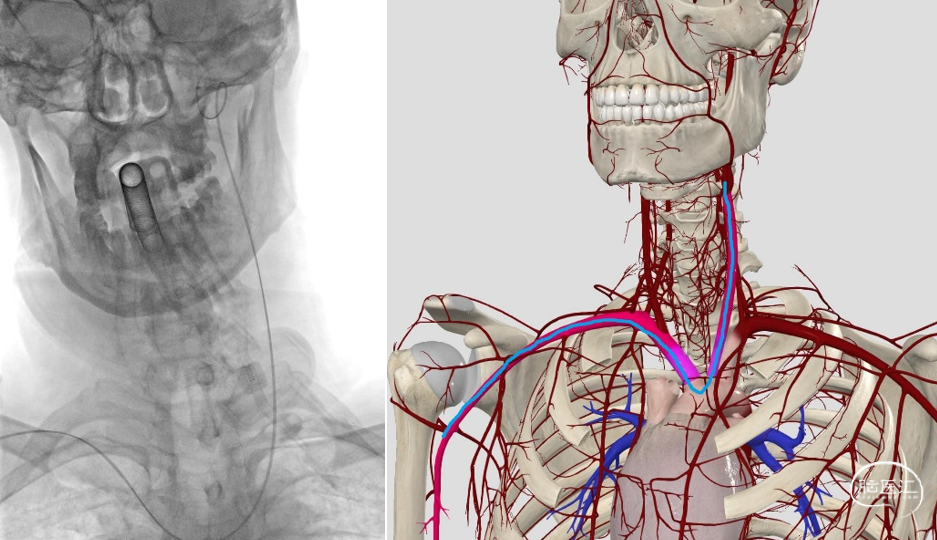

经桡入路的神经介入诊疗目前已成为神经介入的热点话题,什么样的患者适合经桡入路进行治疗目前尚无定论,临沂市人民医院单中心经验认为:在可以假设稳定的诊疗路径的前提下,颅内大血管的重度狭窄诊疗治疗均可以考虑桡动脉入路,该例患者的路径建立难度主要在于需要经右侧桡动脉入路至左侧大脑中动脉的诊疗路径,因患者右侧头臂干和左侧颈总动脉的长轴角度偏小(<70度),难点在于如何保证通路在主动脉弓这一段的稳定性,因此术者支架选用了顺应性更好地中间导管直接建立通路,原因有二:

如果我们选择了6F导引导管作为通路导管,因管路较硬,路径建立过程中无法通过患者左侧颈内动脉入路上的360°环形弯道,因此6F导引导管的到位高度受限,随后的Fastunnel®输送型球囊扩张导管的到位可能会困难,从而无法完成诊疗,即便是内衬5F中间导管后越过了360°的弯道,因5F中间导管的内腔较小,21系统 Fastunnel®到位后占据了5F中间导管的大部分内腔后,术中造影后冒烟定位就会有困难,不利于支架的定位释放;

直接选了6F中间导管作为通路系统,虽然其在弓上的韧性会让人担心,但是利用长交换导丝调整张力后,6F中间导管更好地柔软度反而可以更好地适应患者的II型主动脉弓,保持其在主动脉弓段的稳定性,同时,可以利用泥鳅导丝的支撑力顺利越过左侧颈内动脉的360°环形弯道尽力稳定的诊疗通路,术中的操作也证实了术前的考虑。因此,此例患者治疗的第一核心步骤就是——建立稳定的诊疗通路。